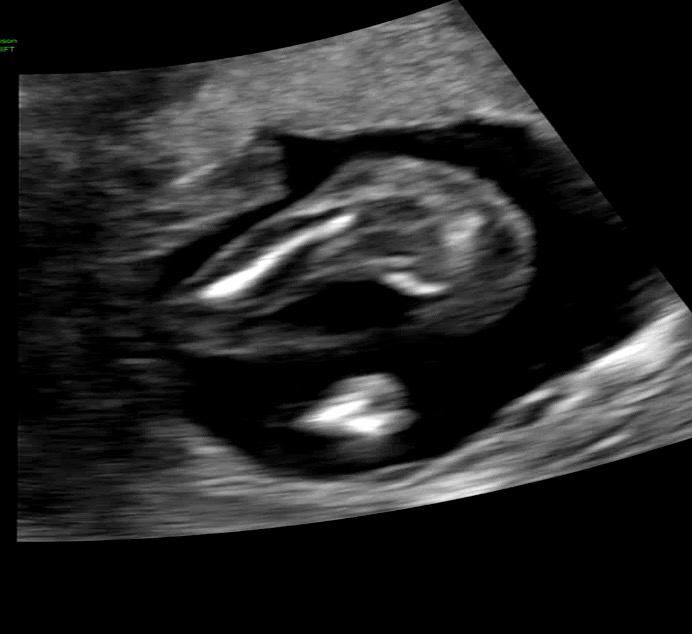

선생님께서 공주님 80퍼라고 하셨는데 딸을 너무 원해서요ㅠㅠ16주에 초음파 봤습니당